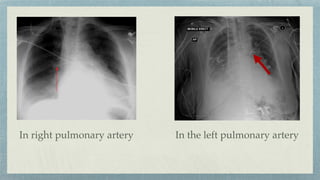

Swan- Ganz Catheter

To monitor pulmonary arterial/ capillary wedge

pressure

Right heart pressures

Cardiac Vs Non-cardiac pulmonary edema

Position:- Main or Lobar pulmonary artery

In the pulmonary artery

In the left pulmonary artery

In right pulmonary artery

Wedge shaped opacity C/L lung collapse